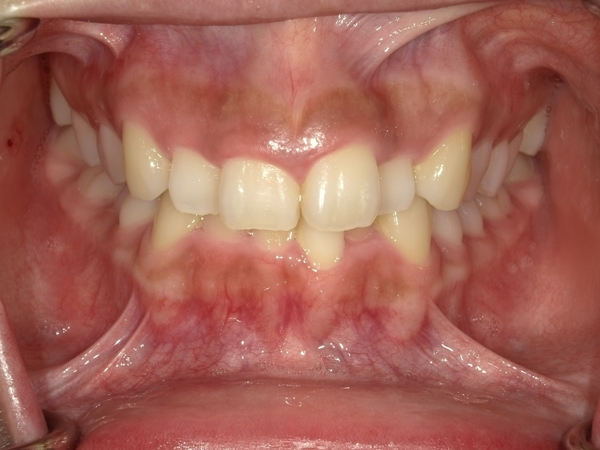

ガタガタとした歯並びや八重歯(叢生)CASE51